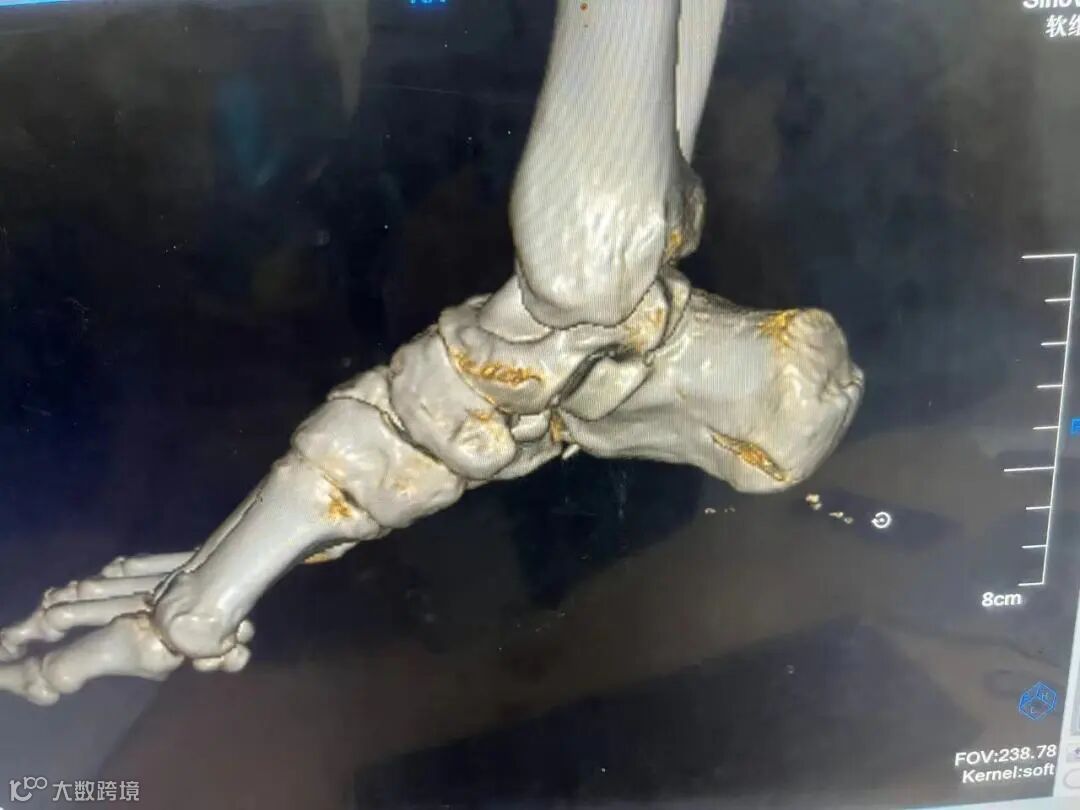

CT结果显示切割伤口深达跟骨3厘米,可能有碎骨存在。救治小组考虑到脚割伤出现大出血必须先止血,如果失血过多会影响生命,救治小组讨论决定,立即予以查找到出血动脉结扎止血清创缝合。

外科韦成业医师主刀手术,术中查找到4处直径约1毫米动脉喷血点,马上结扎止血,术中可见并处理2粒直径约1毫米碎骨,仔细检查可见被切的骨骼肌肌腱和肌腹大部分呈纵向,术中对受伤跟腱、肌腱和肌腹做修复处理,对切缘各层仔细分层对齐缝合,经过近1小时手术,终于成功结扎止血缝合切口。